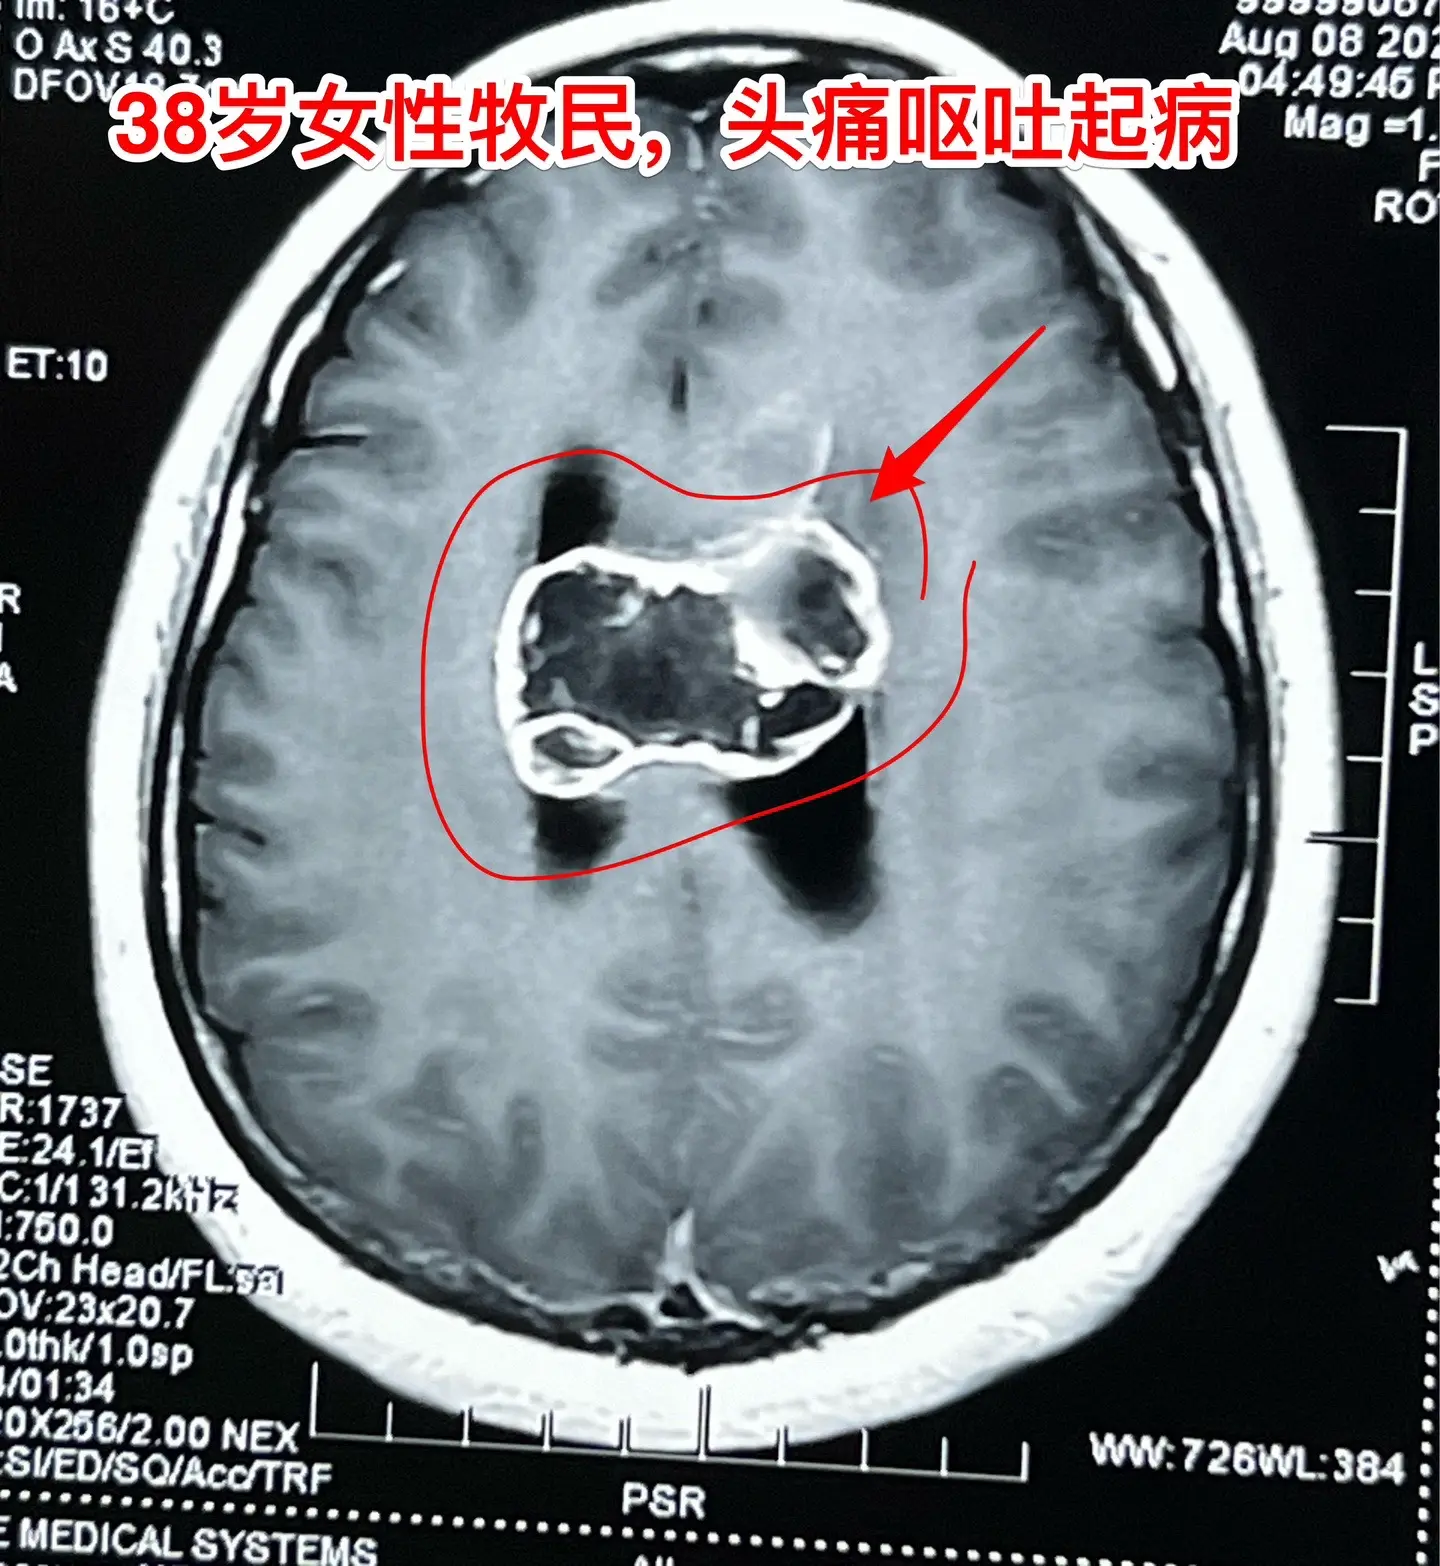

38岁女性脑部发现肿瘤、平时心跳很慢。38岁女性,西乌珠穆沁旗牧民,因头痛、呕吐10天,在锡林浩特市检查发现脑部肿瘤,遂到北京三博脑科医院来作手术。 脑部肿瘤见图,考虑是胶质瘤,肿瘤起源于胼胝体,胼胝体受肿瘤侵蚀,手术前病人的语言和智能没有明显障碍。 在手术准备过程中,发现 病人的心跳很慢,平常才41次/分,夜间最慢慢到31次/分。诊断为窦性心动过缓,为了确保手术安全,不得不临时安放心脏起搏器。 8月9日顺利完成肿瘤切除手术。手术过程很顺利。术中快速冰冻病理报告为胶质母细胞瘤。术后病人很快就清醒了。术后四肢活动无障碍,语言能力和智能情况需要详细评估。